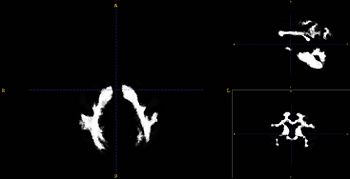

| − | Image:WMtemplate_cr.jpg|Probabilistic map of WM for Rhesus population | + | Image:WMtemplate_cr.jpg|Probabilistic map of WM for Rhesus population|right |

- Using a rhesus tissue atlas provided by the UNC Neuro Image Analysis Laboratory and the UWisc Harlow Primate Laboratory we have segmented the data into WM/GM, and CSF capartments using the Lobulated EM Segmentation method. These segmentations have been averaged to create a study-specific tissue atlas.

- Rhesus Probabilistic Atlas